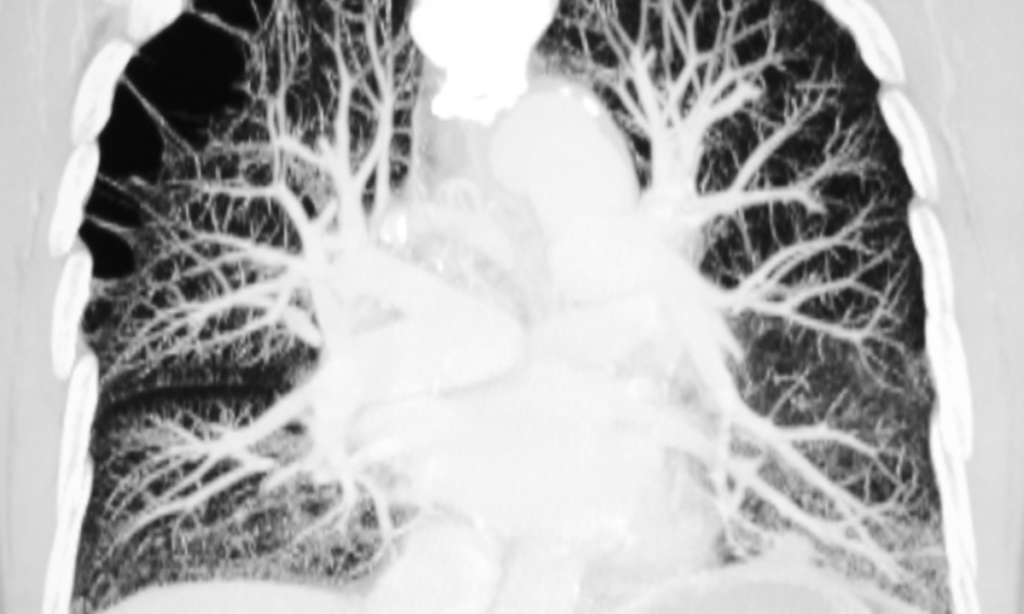

Je nach Grunderkrankung steht das arterielle Gefässsystem der Lunge unter gehörigem Druck.

Pulmonale Hypertonien sind in rund 90 Prozent der Fälle auf Linksherzschäden, Lungenerkrankungen oder Hypoxie zurückzuführen. Sie betreffen also Patienten, die in den Studien zur medikamentösen Therapie praktisch nicht vertreten waren, da sich diese auf die pulmonal arterielle Hypertonie (PAH) beschränkten. Im Hinblick auf eine spezifische Behandlung muss man also genau differenzieren, welche Form der pulmonalen Hypertonie im Einzelfall vorliegt.